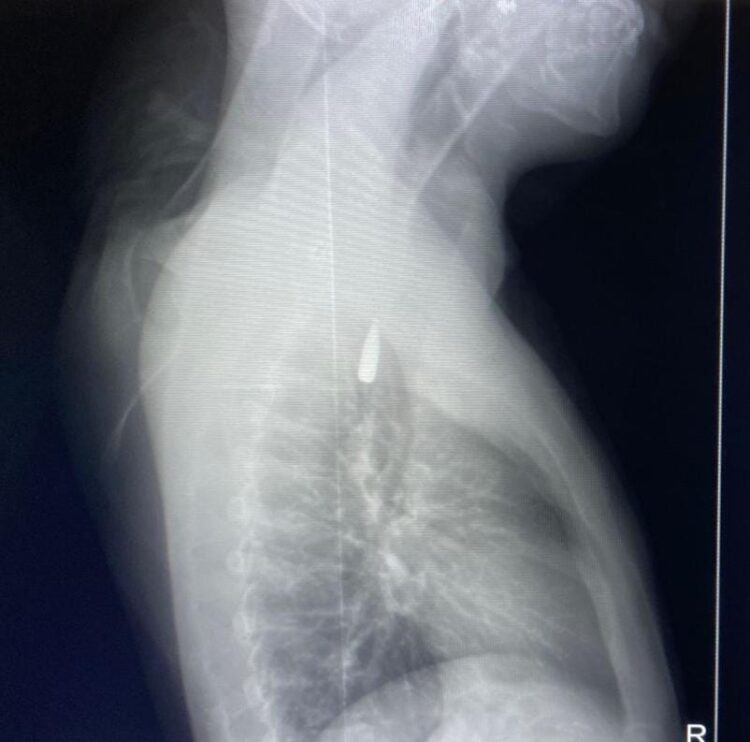

وأوضح الدكتور تامر عبد الله، عميد كلية الطب ورئيس مجلس إدارة المستشفيات الجامعية، أنه في يوم 21 أكتوبر 2025 تمكن فريق من أطباء قسم جراحة القلب والصدر والتخدير والمعاونين من إجراء جراحة دقيقة بالغة الخطورة لأحد المرضى المحجوزين من قطاع غزة،

والذي كان قد تعرض لإصابة بطلق ناري في الرأس منذ فترة، استقر المقذوف على إثرها داخل تجويف القفص الصدري قرب الشريان الأورطي، وهو أكبر وأهم شرايين الجسم والمسؤول عن تغذية جميع الأعضاء الحيوية، وأضاف أن الفريق الطبي، رغم دقة الحالة وتعقيدها، نجح في استخراج المقذوف بأمان بعد عملية جراحية نادرة استمرت عدة ساعات داخل المستشفى الجامعي الجديد،

حيث خضع المريض بعدها للرعاية الطبية اللازمة، وحالته حاليًا مستقرة وتحت المتابعة الدقيقة من الفريق المختص.